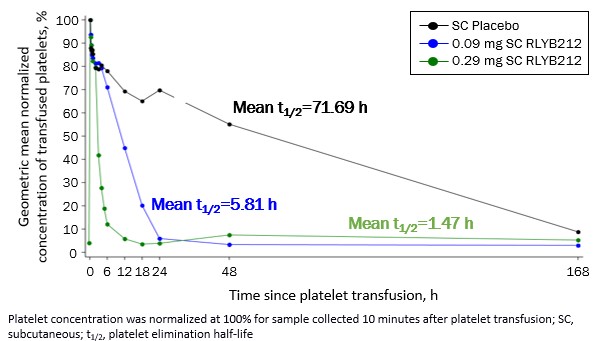

The Phase 1b single-blind, placebo-controlled proof-of-concept clinical trial was designed to establish the ability of SC RLYB212 to rapidly eliminate HPA-1a positive platelets transfused to HPA-1a negative healthy subjects. The study included 11 males aged 18 to 65 years, randomized to RLYB212 0.09mg (n=4), RLYB212 0.29mg (n=5), or placebo (n=2). We reported top-line results from this trial at the 31st Congress of the International Society on Thrombosis and Haemostasis ("ISTH") in the second quarter of 2023 and announced publication of the complete dataset in Thrombosis and Haemostasis in the third quarter of 2024. The results showed that SC RLYB212 administration produced a dose-dependent, rapid, and complete elimination of transfused HPA-1a positive platelets in HPA-1a negative subjects, with both doses meeting the prespecified proof-of-concept criteria of ≥90% reduction in mean platelet elimination half-life. Mean platelet elimination half-life was 5.8 hours (0.09mg dose) and 1.5 hours (0.29mg dose) for RLYB212 compared to 71.7 hours for placebo. Consistent with the Phase 1 first-in-human trial, RLYB212 was observed to be well-tolerated with no reports of serious or severe adverse events.

The Phase 1b single-blind, placebo-controlled proof-of-concept trial was designed to establish the ability of SC RLYB212 to rapidly eliminate HPA-1a positive platelets transfused to HPA-1a negative healthy subjects. The study included 11 males aged 18 to 65 years, randomized to RLYB212 0.09 mg (n=4), RLYB212 0.29 mg (n=5), or placebo (n=2). The study design and results are summarized below.

RLYB212 Phase 1b Trial — Design and Results